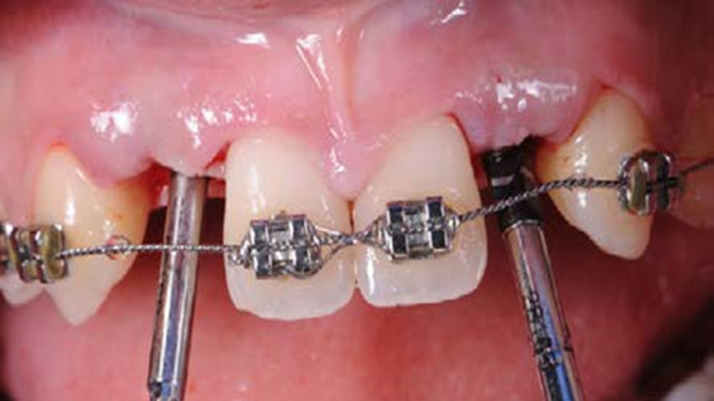

Clinical case: Patient-centered approach: treatment strategy for Root Membrane Technique & delayed implant placement

- Courtesy of Dr. Yoshiharu Hayashi, Japan -

Socket Shield Technique, anterior esthetics, maxillary anterior, esthetic, esthetics, delayed implant placement, socket preservation, AnyRidge, Root Membrane Kit, Root Membrane Technique, Partial Extraction Therapy, PET, esthetic zone, fuse abutment, Dr. Yoshiharu Hayashi,#11,#21,#22

AnyRidge implant system, fuse abutment Root membrane kit, PET Kit